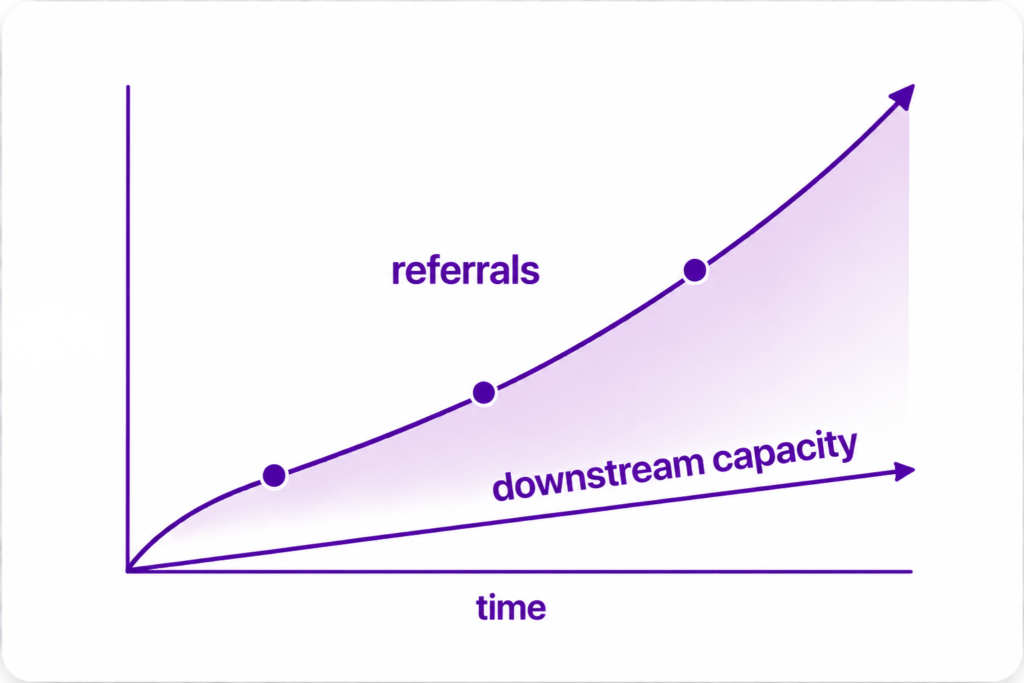

- Skin cancer referrals keep rising.

Specialist capacity does not. - Over 800,000 urgent skin cancer referrals are now made annually in England. More than 90% ultimately prove to be benign

- The pressure downstream is obvious.

The causes often begin upstream